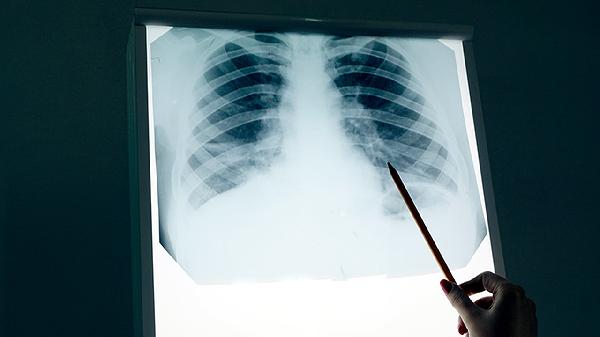

支气管增厚不一定是肺癌,可能由多种原因引起,主要包括慢性炎症、感染性疾病、良性肿瘤、环境刺激物影响及肺癌等。支气管增厚指支气管壁结构在影像学检查中显示异常增宽,常作为呼吸道疾病的间接征象。

支气管肺癌肿瘤细胞浸润可直接导致管壁不规则增厚,多见于鳞状细胞癌或小细胞肺癌。这类增厚常伴有咯血、胸痛等警示症状。确诊需结合病理活检,治疗包括手术切除或靶向药物治疗。

发现支气管增厚应完善支气管镜检查及病理活检以明确性质,日常生活中需严格戒烟并佩戴口罩防护呼吸道,保持室内空气流通,避免接触化工粉尘等有害物质,定期进行低剂量螺旋CT筛查有助于早期发现恶性病变。出现持续咳嗽、声音嘶哑或胸痛等症状时应及时前往呼吸内科就诊。